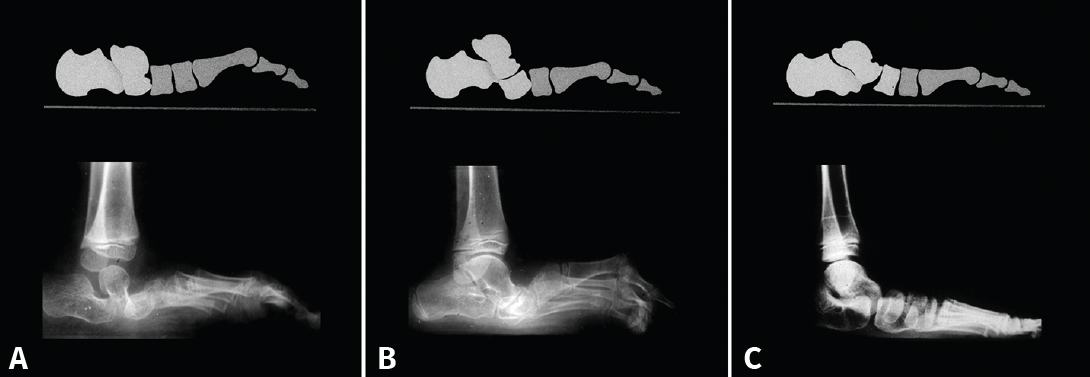

Figura 3. A: pie plano astrágalo vertical. Inflexión en la articulación talonavicular; B: pie plano paralítico. Inflexión en la articulación navículo-cuneiforme medial; C: inflexión en todas las articulaciones del arco interno: talonavicular, navículo-cuneiforme medial, primera articulación tarsometatarsiana.

En el pie plano, el doble movimiento de rotación en sentido inverso que se produce conlleva que en la columna interna del pie se produzca algún tipo de subluxación o luxación. La localización de esta tendrá relación con la etiología de cada pie plano(6): en el pie plano astrágalo vertical se produce a nivel de la talonavicular, en el pie paralítico (secuelas de poliomielitis) a nivel de la articulación navículo-cuneiforme y, en los pies planos laxos infantiles, en todas las articulaciones de la columna interna del pie: talonavicular, navículo-cuneiforme y 1.ª ATMT (Figura 3).